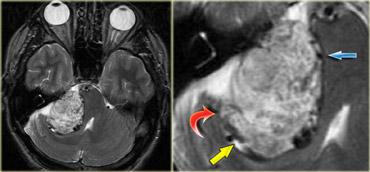

U thần kinh bao (Schwannoma) vùng góc cầu tiểu não với các đặc điểm điển hình của u ngoài trục (Chuỗi xung T2W)

Chuỗi xung T2W cho thấy một u thần kinh bao (schwannoma) nằm ở góc cầu tiểu não (CPA).

Trường hợp này minh họa rõ nét các dấu hiệu điển hình của u ngoài trục.

Có khe dịch não tủy (mũi tên vàng).

Các mạch máu dưới nhện chạy trên bề mặt não bị tổn thương đẩy lệch (mũi tên xanh lam).

Có chất xám nằm giữa tổn thương và chất trắng (mũi tên đỏ cong).

Khoang dưới nhện bị giãn rộng do sự phát triển của tổn thương ngoài trục có xu hướng đẩy lùi não.

Tất cả các dấu hiệu này cho thấy đây là một u ngoài trục điển hình.

Tại vùng góc cầu tiểu não, 90% các u ngoài trục là u thần kinh bao (schwannoma).